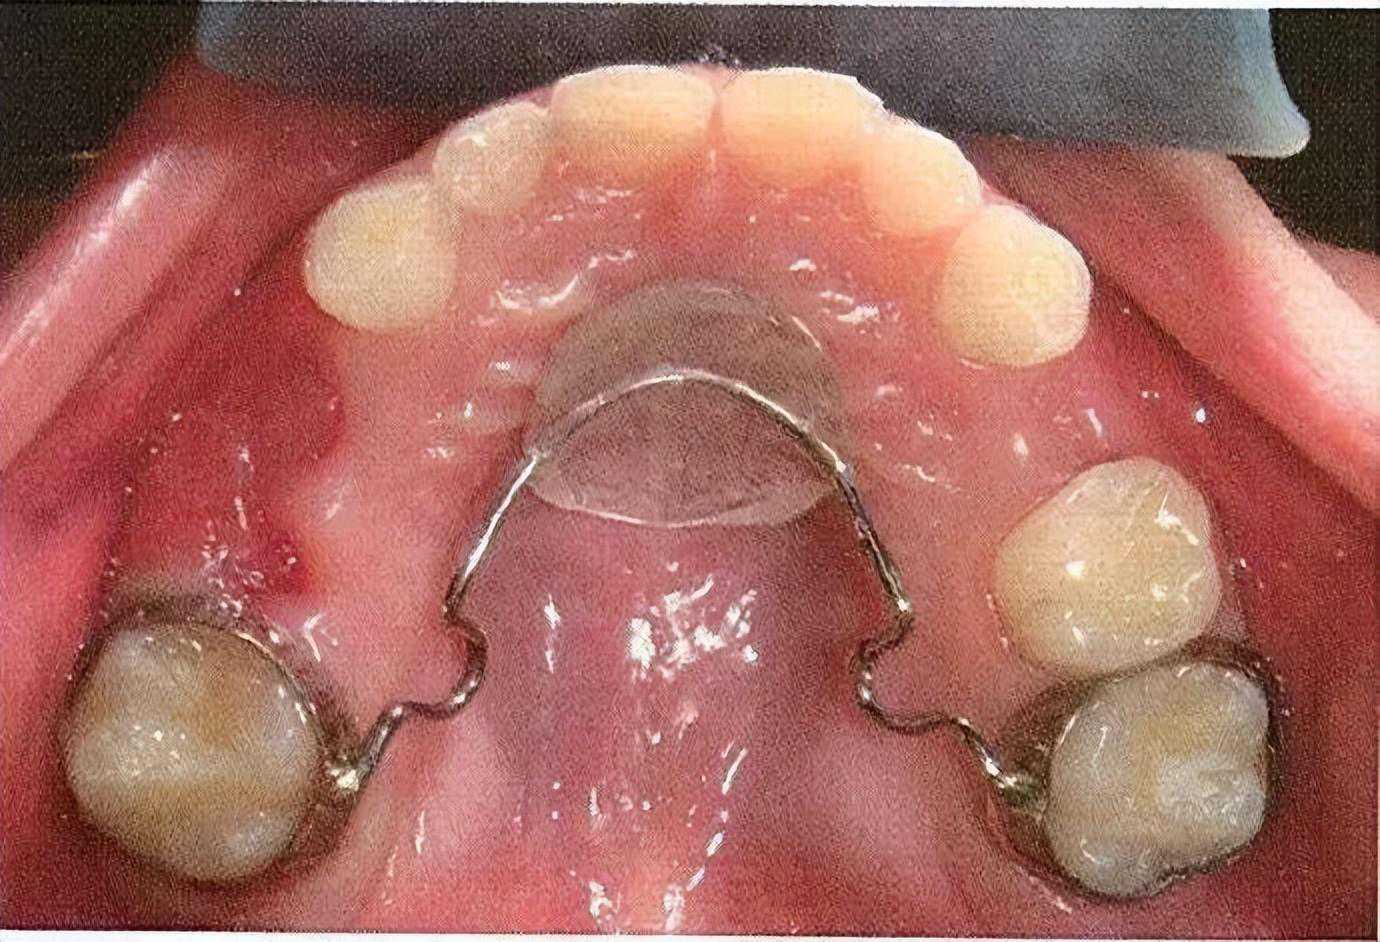

所以面对乳牙早失,我们就需要制作间隙保持器来维持这个空缺。如下图这样,间隙保持器可以占据缺失牙齿在牙列中的位置,保留继承恒牙萌出所需的空间。

2.舌弓/腭弓式间隙保持器:两端通过带环固定在两侧缺失牙后方的牙齿上,常用于左右两侧都有缺牙或单侧缺失2颗牙齿且不适合做丝圈式间隙保持器的情况。